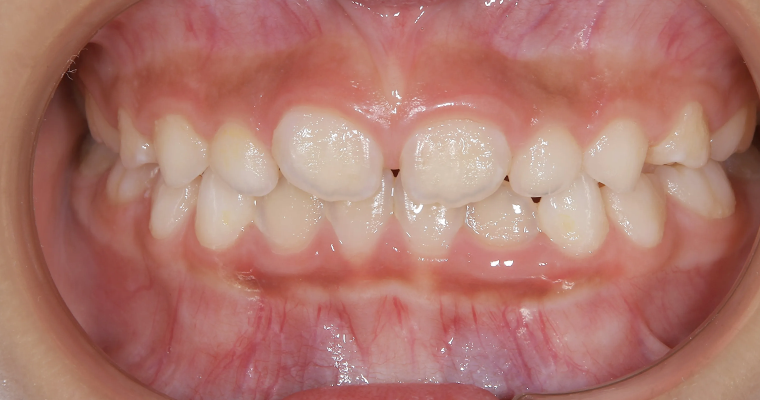

正面観

BEFORE

AFTER

| 主訴 | 歯並びが悪い 乳歯と永久歯が重なっている 歯がまっすぐはえてこない |

|---|---|

| 治療期間 | 6-7ヶ月 |

| 治療費 | 440,000円(税込) ※調整、器具、治療後にお渡しするEFLine(矯正後の後戻りを防ぐ器具)も全て込みでの金額となっております。 |

| 治療内容 | 拡大床矯正 EF Lineで筋機能療法 |